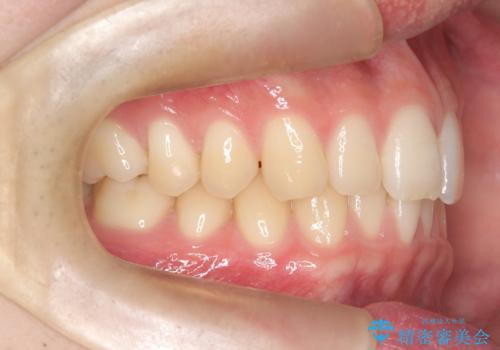

上顎中切歯間の隙間の他にもフロスが抵抗なく入るスペースが上顎は数か所ありました。スペースを閉じ下顎の歯列弓との調和をとるためIPRを行いました。

下顎の舌側傾斜気味の前歯も唇側へ歯軸傾斜させています。